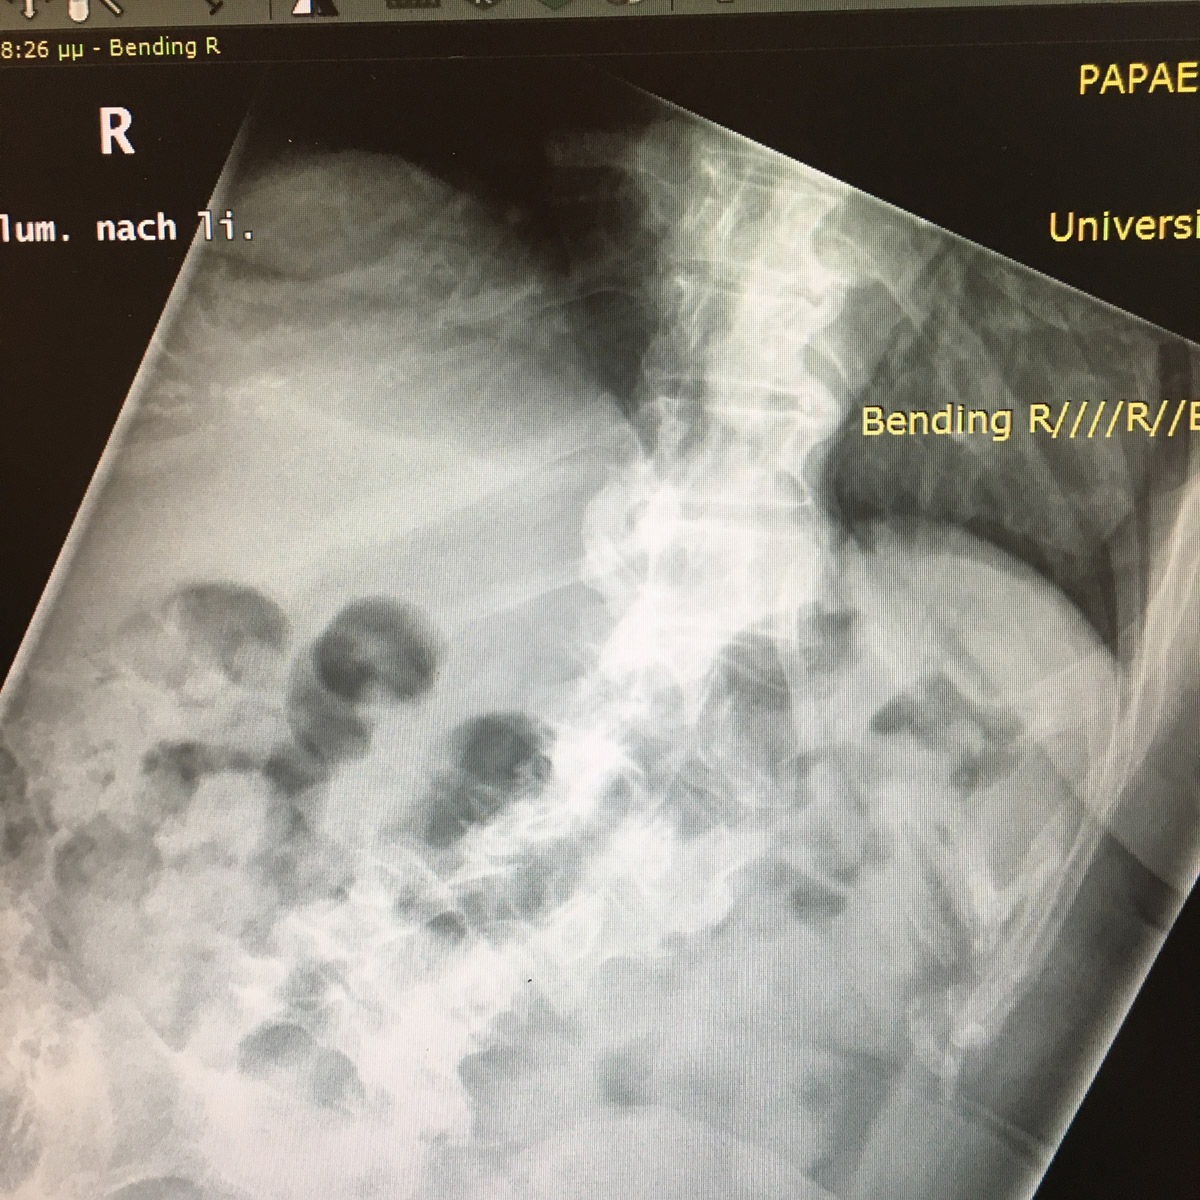

Εικ 1: Προεχειρητικές ακτινογραφίες της σπονδυλικής στήλης σε όρθια στάση. α) Ουδέτερη θέση β) Κάμψη Αριστερά

Παρατηρείται: Δεξιά θωρακική σκολίωση 33 μοιρών κατά Cobb, αριστερή θωρακο-οσφυϊκή 15 μοιρών και δεξιά οσφυϊκή 27 μοιρών.